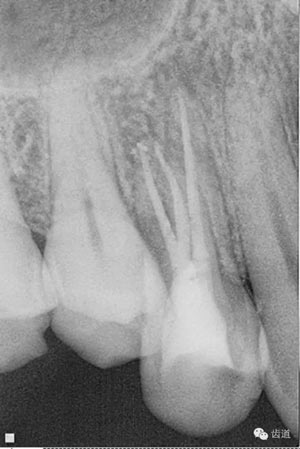

處理:顯微根管治療。放置橡皮障,去除暫封,顯微鏡下超聲去除頰側(cè)根管上段部分牙本質(zhì),探及遠(yuǎn)中根管口,見(jiàn)有糊劑遮蓋。Path file根管疏通,M Two根管預(yù)備至2506#,配合3%次氯酸鈉和17%EDTA超聲蕩洗,干燥根管,放置氫氧化鈣糊劑,zoe暫封。

檢查:暫封完好,牙齦無(wú)紅腫。叩診-。

處理:放置橡皮障,去除暫封,超聲結(jié)合2%CHX清除遠(yuǎn)頰根管內(nèi)氫氧化鈣糊劑,主牙膠試合后95%酒精沖洗干燥根管,結(jié)合AH Plus糊劑連續(xù)波熱牙膠垂直加壓充填根管,樹(shù)脂分層粘接修復(fù)牙體。建議定時(shí)復(fù)診進(jìn)行嵌體修復(fù),患者未執(zhí)行。